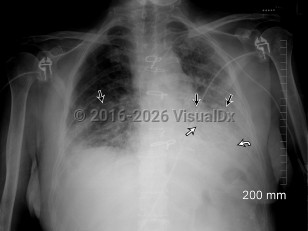

Imaging Studies image of Acute interstitial pneumonia - imageId=8345960. Click to open in gallery.  caption: '<span>Single portable semi-upright  AP view of the chest. There are bilateral airspace opacities with a  predominantly lower lobe distribution, left greater than right (straight  black arrows). An air bronchogram is also evident within the left lung  (straight white arrow). There is a craniocaudal gradation of density  which suggests pleural effusions, although this is difficult to  appreciate on a semi-recumbent exam (curved white arrow). Follow-up CT  confirmed bilateral pleural effusions, left greater than right.</span>'

Single portable semi-upright AP view of the chest. There are bilateral airspace opacities with a predominantly lower lobe distribution, left greater than right (straight black arrows). An air bronchogram is also evident within the left lung (straight white arrow). There is a craniocaudal gradation of density which suggests pleural effusions, although this is difficult to appreciate on a semi-recumbent exam (curved white arrow). Follow-up CT confirmed bilateral pleural effusions, left greater than right.